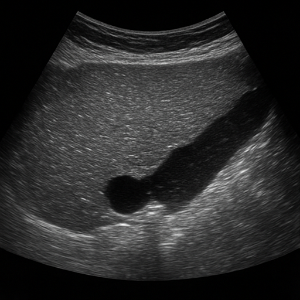

담낭과 담관

담낭은 담석이나 담낭염, 담낭 벽 두께 변화 등을 확인하는 데 아주 유용하답니다. 담관의 확장이나 폐쇄 여부도 복부초음파로 간접적으로 알아볼 수 있어요.

담석증과 담낭염

- 담석증

담낭 안에 작은 돌이 생긴 거예요. 초음파에는 그림자처럼 뚜렷하게 나타나서 찾기 쉬워요. - 담낭염

담낭에 염증이 생기는 것으로, 두꺼워진 벽이나 주변에 생긴 변화가 화면에 보여요.